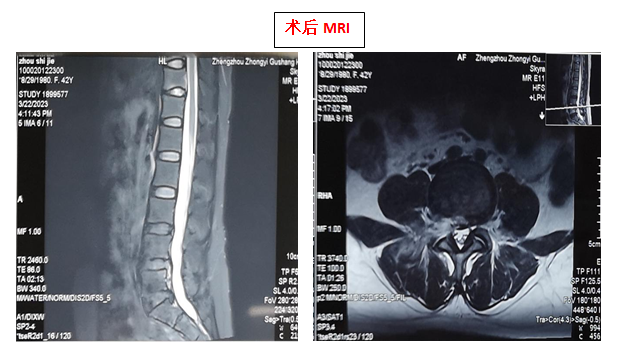

42 岁的张女士(化名),半个月前劳累后突然出现腰痛伴右下肢疼痛麻木,休息后症状无缓解,腰椎 MRI 检查提示:腰椎间盘突出(L4/5),长期保守治疗后症状无明显缓解。后就诊郑州中医骨伤病医院,门诊医师检查后以「腰椎间盘突出症」为诊断收住急诊外科。

与患者及家属充分沟通后建议行椎间孔镜微创手术治疗,在局麻强化下行「全可视下椎间孔镜腰椎间盘突出髓核摘除术」治疗。术后即可基本恢复正常行走。